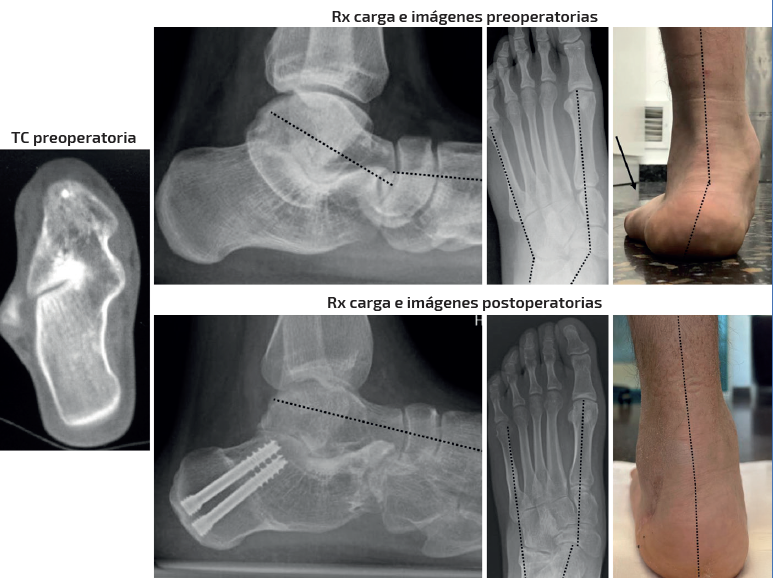

Caso 2 (Figura 5)

Se trata de un paciente varón de 26 años. Clínica de dolor medial y pinzamiento subfibular. Coalición talocalcánea ósea completa. Deformidad en plano, valgo y abducto. Tipo IIB de Myerson. Tratamiento: doble osteotomía del calcáneo (alargamiento de la columna externa + deslizamiento medial) + osteotomía de Cotton. Aloinjerto liofilizado de cresta. Seguimiento: 2,5 años. Mejoría en la alineación clínica y el dolor. Destaca la mejoría en los parámetros radiológicos del retropié tanto dosoplantares como sagitales a pesar de la coalición ósea. Nota: caso cedido por Dr. F. J. Carrillo Piñero).